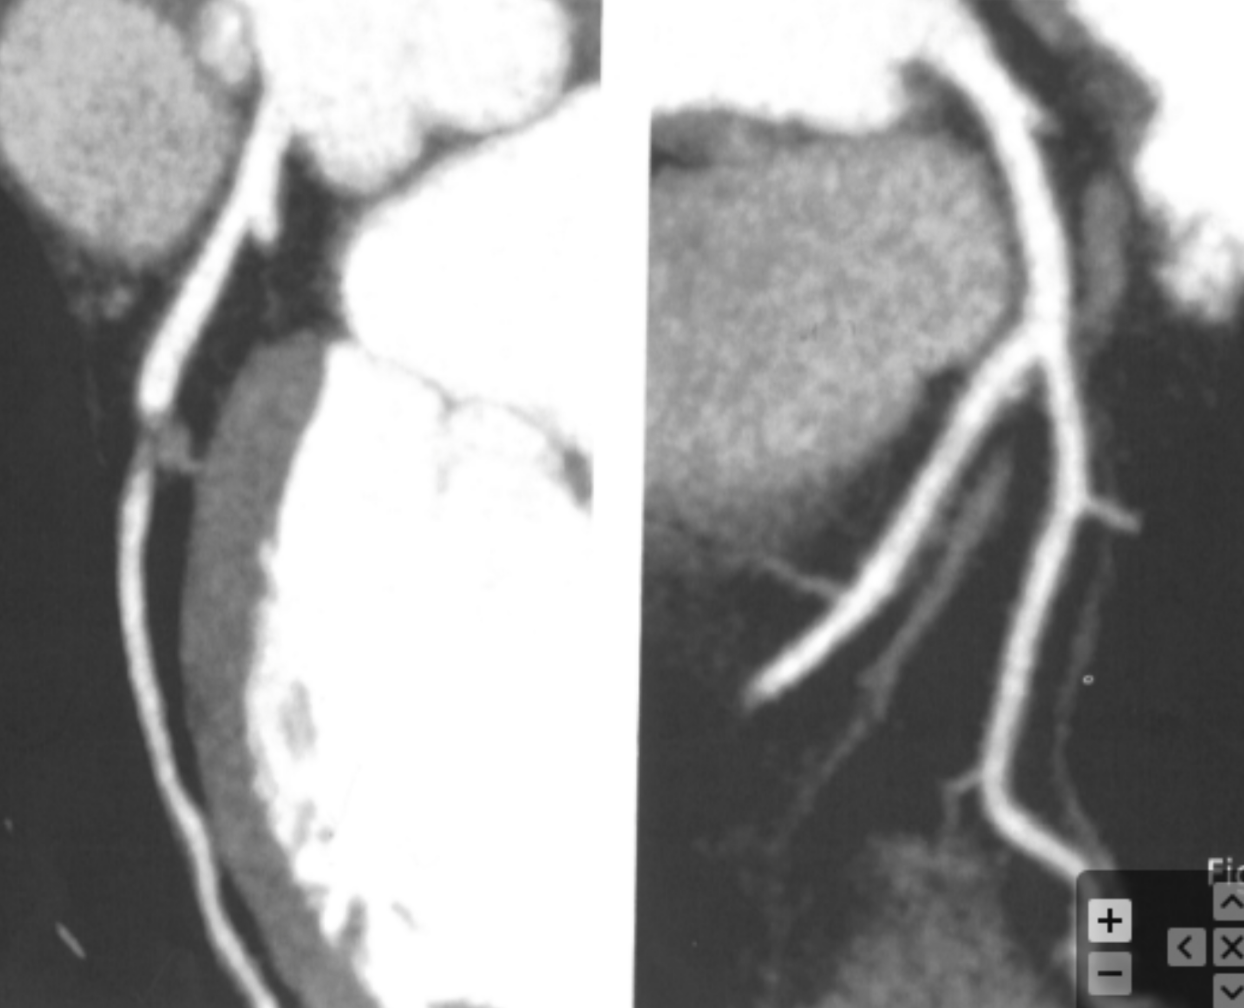

Based on the comparative appearance of these two images, what element of the reconstruction was modified during the second reconstruction?

Slice Thickness